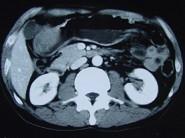

问题 女性,42岁,腹痛、黑便1周,CT扫描见胃窦部圆形块影,最佳的诊断是()

选项 A.胃窦平滑肌瘤 B.胃癌 C.胃淋巴瘤 D.胃窦神经纤维瘤 E.胃内异物

答案 D